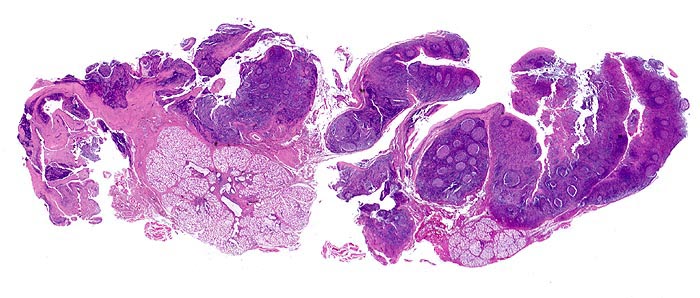

infektiöse Mononukleose

Tonsille

Aktivierung der B-Lymphozyten-Areale (EBV induzierte Infektion und Stimulation der EBV-Rezeptor tragenden B-Zellen): grosse, aktivierte Keimzentren (= follikuläre Hyperplasie).

Aktivierung der T-Lymphozyten-Areale (Virusantigen-induzierte Aktivierung der spezifischen antiviralen T-Zell Antwort): interfollikuläre Hyperplasie. Speicheldrüsen.

Tonsillektomie bei einem Studenten mit Angina, Lymphknotenschwellungen und einer Lymphozytose im Blut.